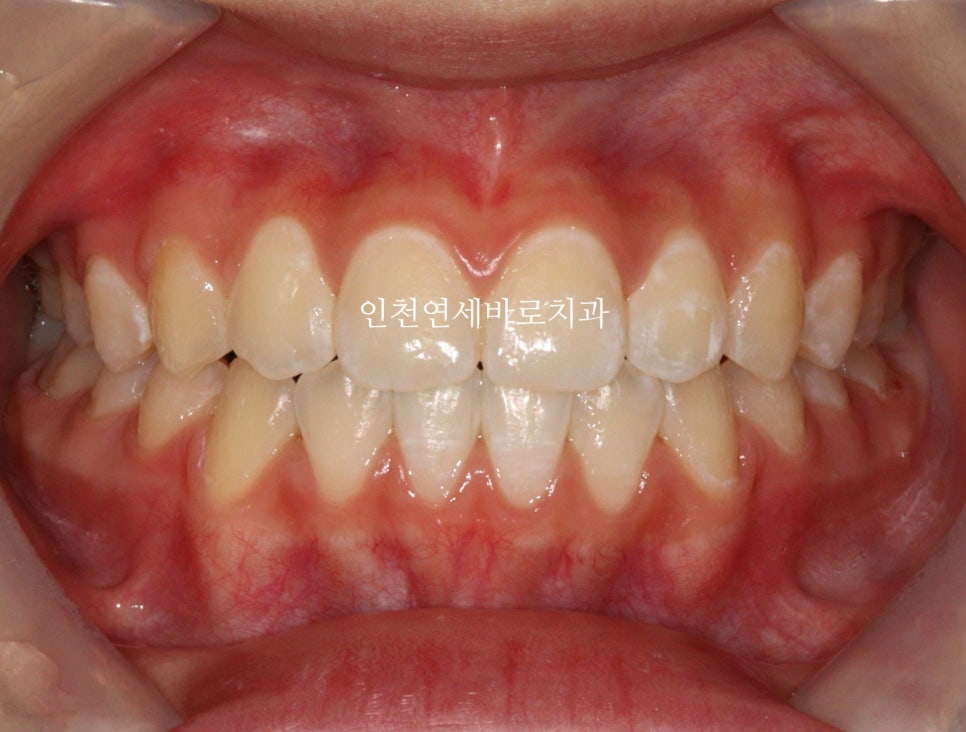

두번째 치아가 덧니로 있는 경우의 치료는 흔한 경우지만

생각보다 많은 노하우가 필요한 치료라고 생각합니다.

전 후 비교

치아배열도 좋습니다.